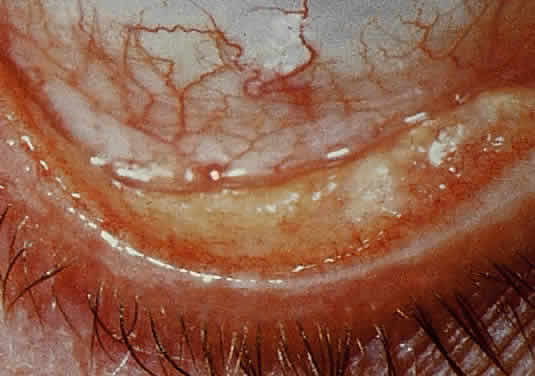

CONJUNCTIVA. Clinically detectable conjunctival involvement is not a feature of systemic amyloidosis. However, nonfamilial amyloidosis confined to the conjunctiva has been reported as an example of primary amyloidosis. Conjunctival amyloidosis is often asymptomatic and may be present for years before the patient seeks medical attention. Typically, there is a discrete, nonulcerative, yellow, waxy, firm, nontender subconjunctival swelling (Fig. 8). This may be located in the palpebral fornix or bulbar conjunctiva, including the limbal area. The conjunctival area is usually smooth but may be friable and may show recurrent bleeding. However, antecedent local diseases have been incriminated in this amyloid deposition.77